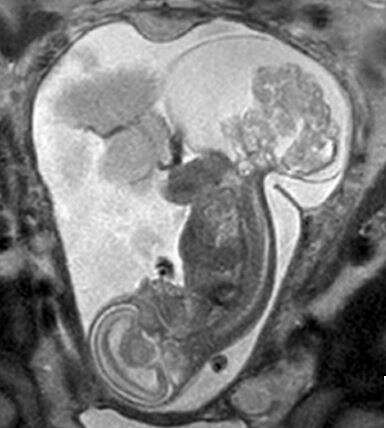

זוהתה טרטומה בעמוד השדרה  // צילום: מרגרט בומר

"הרופאים זיהו משהו בסריקה" סיפרה האם, "והרופא בא ואמר לנו שיש משהו מאוד לא בסדר עם התינוקת שלנו. הוא אמר שיש לה 'טרטומה'" (teratoma sacrococcygeal).

ד"ר דארל קאס הסביר כי טרטומה הוא הגידול השכיח ביותר בקרב תינוקות, אך גם הוא נחשב ל"די נדיר", המשפיע על אחד מתוך כ-50 אלף לידות.